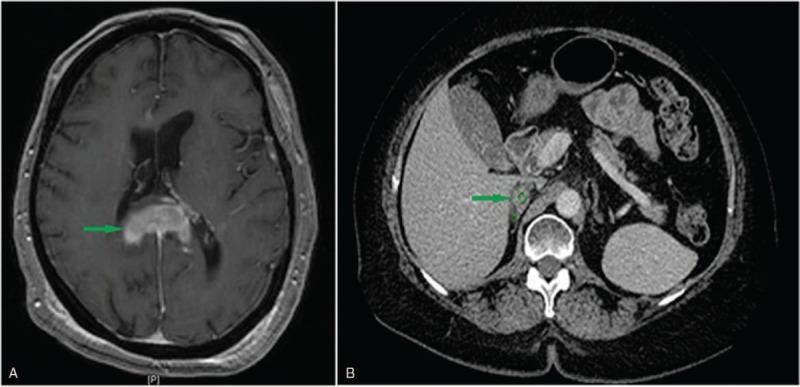

Enhanced magnetic resonance imaging revealed the mass within the splenium of the corpus callosum. On histological examination, there was a diffuse growth pattern of neoplastic cells in the brain biopsy. Immunohistochemistry and flow cytometric analysis demonstrated that the neoplastic cells were of B-cell lineage.

After 4 years of clinical remission, the patient was diagnosed with endometrial cancer. Interestingly, a radiological study following the treatment of endometrial cancer demonstrated a right adrenal mass, which was suspicious for malignancy. Morphologic examination and immunohistochemistry studies confirmed the diagnosis of diffuse large B-cell lymphoma. A fluorescent in situ hybridization panel for lymphoma showed rearrangement of Immunoglobulin heavy chain (IGH) and B-cell lymphoma 6 (BCL6), respectively, suggesting fusion of BCL6/IGH. Immunoglobulin kappa analysis demonstrated a common origin for the brain and adrenal lesions, which led to the final diagnosis of an adrenal relapse of CNS-DLBCL.